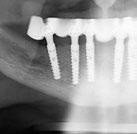

Exploración radiológica

Mediante CBCT constatamos atrofias óseas severas y disminución de soporte óseo periodontal en relación con las piezas dentales.

Uno de los aspectos que nos convenció para utilizar un sistema guiado fue la baja tasa desviación que presentan los implantes. Si bien la cirugía a mano alzada es completamente válida, no estamos exentos de que se produzca una desviación de 11.2° ± 5.6° (5), mientras que usando sistemas guiados, dicha desviación se reduce significativamente a un 2.1° ± 1° (6). Otro factor favorable es que contempla la posición tridimensional ideal (7, 8), teniendo en cuenta el espacio de confort, así como una rehabilitación protésicamente guiada a partir de un encerado diagnóstico digital efectuado sobre referencias anatómicas obtenidas de un CBCT y modelos de estudio tridimensionales a través de un escaneado intraoral. Su uso, sin duda, facilita la fase protésica y reduce significativamente los cambios en el plan de tratamiento protésico, teniendo claro, desde el